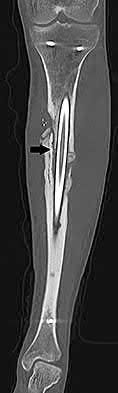

A 72-year-old female on prolonged bisphosphonate therapy presents with thigh pain.

Radiographs show a fracture of the femoral shaft. Which of the following radiographic features is most characteristic of an atypical femur fracture associated with bisphosphonate use?

Explanation

Atypical femur fractures (AFFs) associated with prolonged bisphosphonate therapy have specific major criteria defined by the ASBMR. These include a location anywhere from just distal to the lesser trochanter to just proximal to the supracondylar flare, transverse or short oblique orientation, non-comminuted (or minimally comminuted), and originating at the lateral cortex with localized periosteal or endosteal thickening ('beaking').